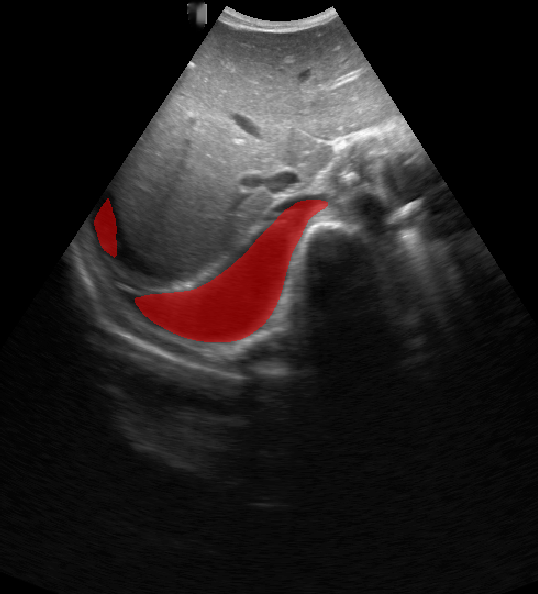

A total of 143 images were acquired from 59 patients. The images were obtained at the left and right PLAPS (PosteroLateral Alveolar and/or Pleural Syndrome) and subcostal views [4] with linear array and curved array (abdominal) ultrasound probes. The data were split according to the use of these probes into two datasets of 51 and 92 images, respectively for linear array and curved array. We denote these datasets as Dataset A (linear array) and Dataset B (curved array). All images were annotated at the time of acquisition to measure the extent of the effusion. These annotations consisted of small crosses at the top and bottom of the deepest area of effusion. See Figure 1 (left column) for example images.

Before being used for training and evaluating the models, each image was automatically cropped using a rectangular/cone mask to remove non-imaging content. Next, we applied an inpainting text algorithm using keras-ocr followed by template matching and edge detection algorithms from opencv to remove the annotations that were added to the images to measure the effusion. Examples of the outputs of this preprocessing are shown in Figure 1 (centre column).

All images in both datasets were manually segmented using the ITK-SNAP software [14] (www.itksnap.org) by a trained observer. Examples of ground truth segmentations are shown in Figure 1 (right column). These segmentations acted as ground truths for training and evaluating the proposed models. Additionally, a second trained observer performed independent segmentations of subsets of 10 random images each from the two datasets. These were used to compute an estimate of inter-observer variability in the manual segmentation process.

Qualitative prediction results of the two proposed models (baseline nnU-Net and nnU-Net with coordinate convolutions) on the two datasets are shown in Figure 2. Tables 1 and 2 summarise the quantitative performances in terms of DSC and area statistics. Histograms of the DSC values are shown in Figure 3. The median DSCs between the manual segmentations on the subsets of 10 images (i.e. the estimates of inter-observer variability) are also shown in Table 1.

Rows 1-2: Dataset A. Rows 3-4: Dataset B.